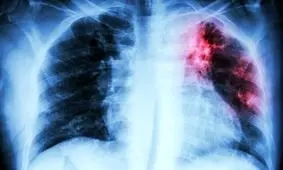

بیماری عفونی سل (TB) سالانه تقریبا جان دو میلیون نفر را در جهان را میگیرد. سل، عفونتی باکتریایی است که عمدتا ریههای…

متخصص بیماریهای عفونی دانشگاه با بیان اینکه سل یک بیماری عفونی مزمن و کشنده اما قابل پیشگیری و درمان است، بر ضرورت…